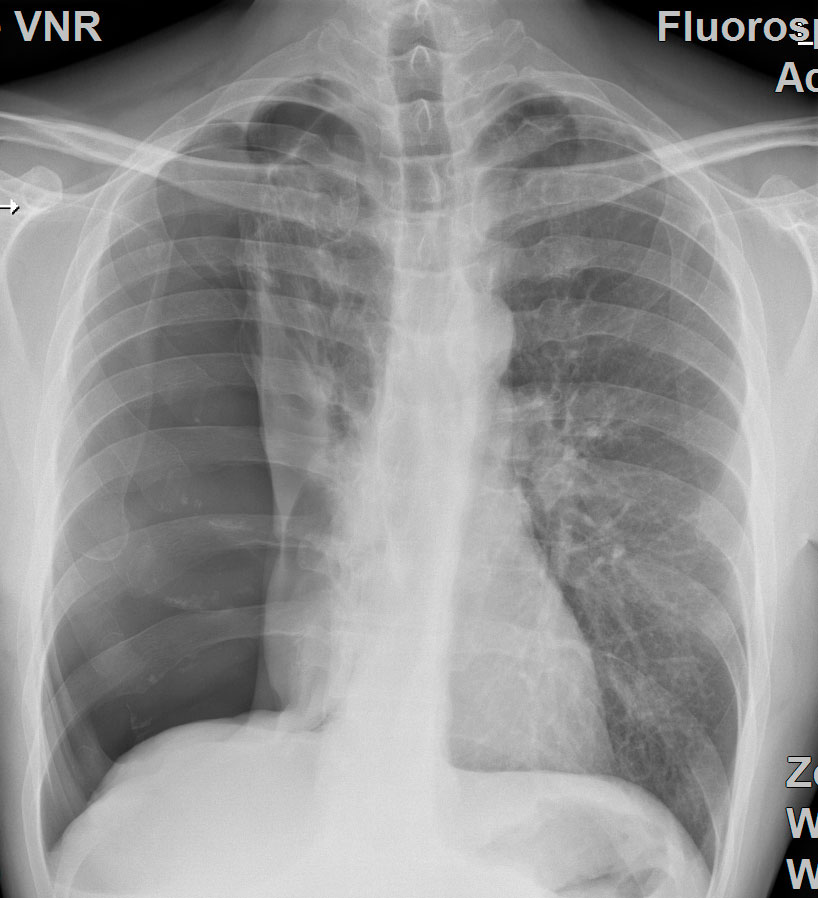

Lungenkollaps (Pneumothorax)

Unter einem Lungenkollaps/Pneumothorax (pneu = Luft, Thorax = Brustkorb) versteht man ein Eindringen von Luft in den Lungenfellraum (Pleuraraum). Die Luft kann von innen oder von außen durch eine Verletzung der Brustwand in den Pleuraraum gelangen. Die Folge davon ist, dass sich die Lunge nicht mehr ausdehnen kann und in sich zusammenfällt. Ursachen hierfür kann ein Rippenbruch, aber auch das Platzen von aufgetriebenem Lungengewebe (Lungenemphysem) sein.

Ursache

Je nach Ursache werden verschiedene Formen des Pneumothorax unterschieden. Im Prinzip gibt es drei grundsätzliche Formen:

- Spontanpneumothorax mit zwei Unterformen:

- primär (idiopathischer, keine vorliegende Lungenerkrankung)

- sekundär (symptomatischer, bekannte Lungenerkrankung)

- Traumatischer Pneumothorax

- Iatrogener Pneumothorax

Die Art der chirurgischen Therapie ist in hohem Maße von der Form des Pneumothorax abhängig.

Pleuraerguss / Pleuraempyem

Als Pleuraerguss wird eine Ansammlung von Flüssigkeit im Brustkorb zwischen der inneren Wand des Brustkorbs und der Lunge bezeichnet. Dadurch wird die Lunge zusammengefaltet und kann die Funktion beeinträchtigt werden. Ein Pleuraempyem bezeichnet eine Eiteransammlung im Pleuraraum (zwischen der Lunge und dem Rippenfell). Unsere Klinik bietet unterschiedliche operative Therapiemöglichkeiten.

Tumornachsorge

Bei der Tumornachsorge geht es darum, nach Therapie eines Krebsleidens eine regelmäßige ärztliche Kontrolle konsequent und dauerhaft durchzuführen. Damit soll bei Patienten mit Lungenkrebs ein erneutes Auftreten des Tumors in der Lunge oder in anderen Organen (Fernmetastasen) frühzeitig zu erkennen. Durch ein frühzeitiges Feststellen eines erneuten Auftretens eines Tumors wird eine frühzeitige Behandlung möglich noch bevor Beschwerden auftreten. In der Nachsorge werden nicht nur körperlichen Symptome, radiologische und Laborkontrollen erfasst, sondern auch psychosoziale Probleme sowie Fragen zur Berufs- und Arbeitsfähigkeit mit dem Patienten diskutiert und Lösungsvorschläge angeboten. Dies geschieht in engem Bezug zum Hausarzt und Lungenfacharzt.